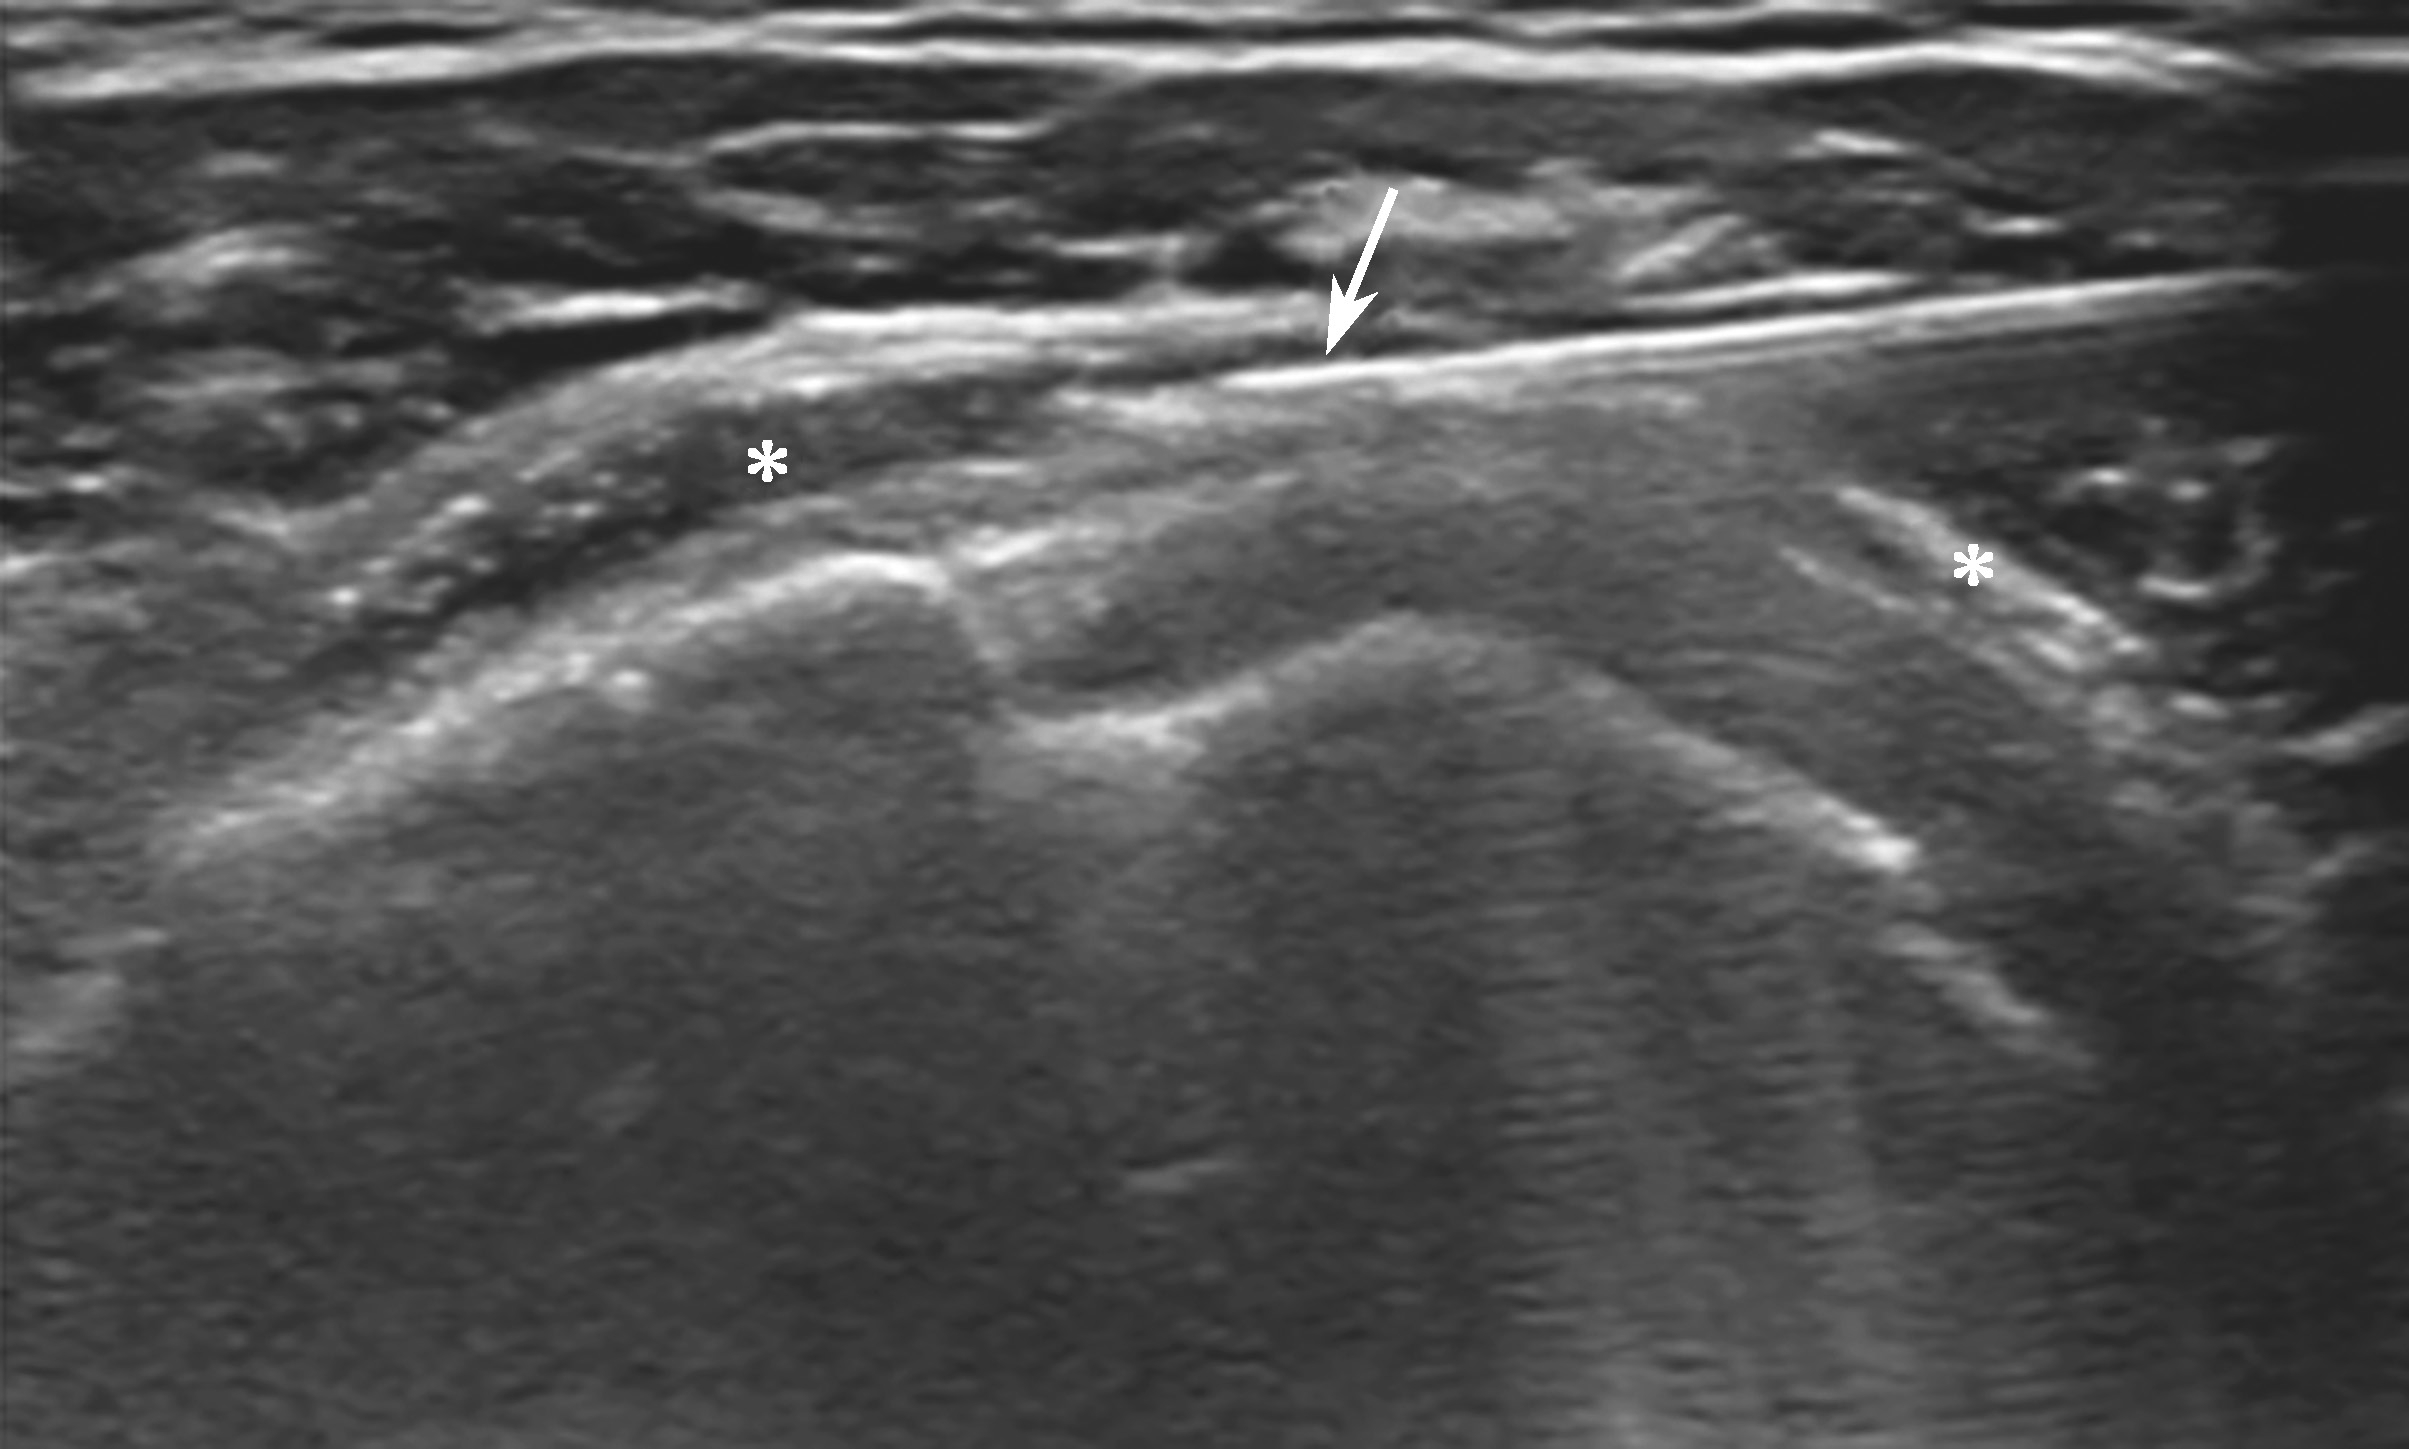

平面内进针法,从内向外或从外向内引导针尖进入滑囊后进行药物注射(图2-1-3、图 2-1-4)。

▲ 图2-1-4 超声引导下肩峰下-三角肌下滑囊注射治疗超声图

箭头:穿刺针;星号:滑囊